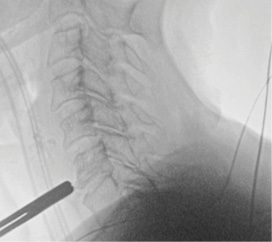

Patient underwent outpatient surgery procedure at our ASC (San Luis Obispo Surgery Center)—a 60-minute procedure with minimal blood loss. She was discharged to home 2.5 hrs after the procedure. She had immediate improvement in right arm strength, and progressive improvement in right arm pain and paresthesias—now 3+ months postop.

Patient is a healthy, active 58 year-old female, though with advanced degenerative spondylosis at a low cervical level. The patient had favorable anatomy with a long neck and low shoulders to facilitate intraoperative visualization. Fusion was appropriate in this case, but intraoperatively, though we were prepared for this possiblity, the disk space was well-preserved and mobilized without major modification of the endplates. The postoperative flexion and extension radiographs showed movement at the spinous processes of C6/7 and good function of the prodisc C Vivo prosthesis. The adjacent C5/6 level also shows degenerative spondylosis. By optimizing the mobility of the C6/7 level I anticipate the patient will have an improved trajectory for her cervical spine function throughout her life.